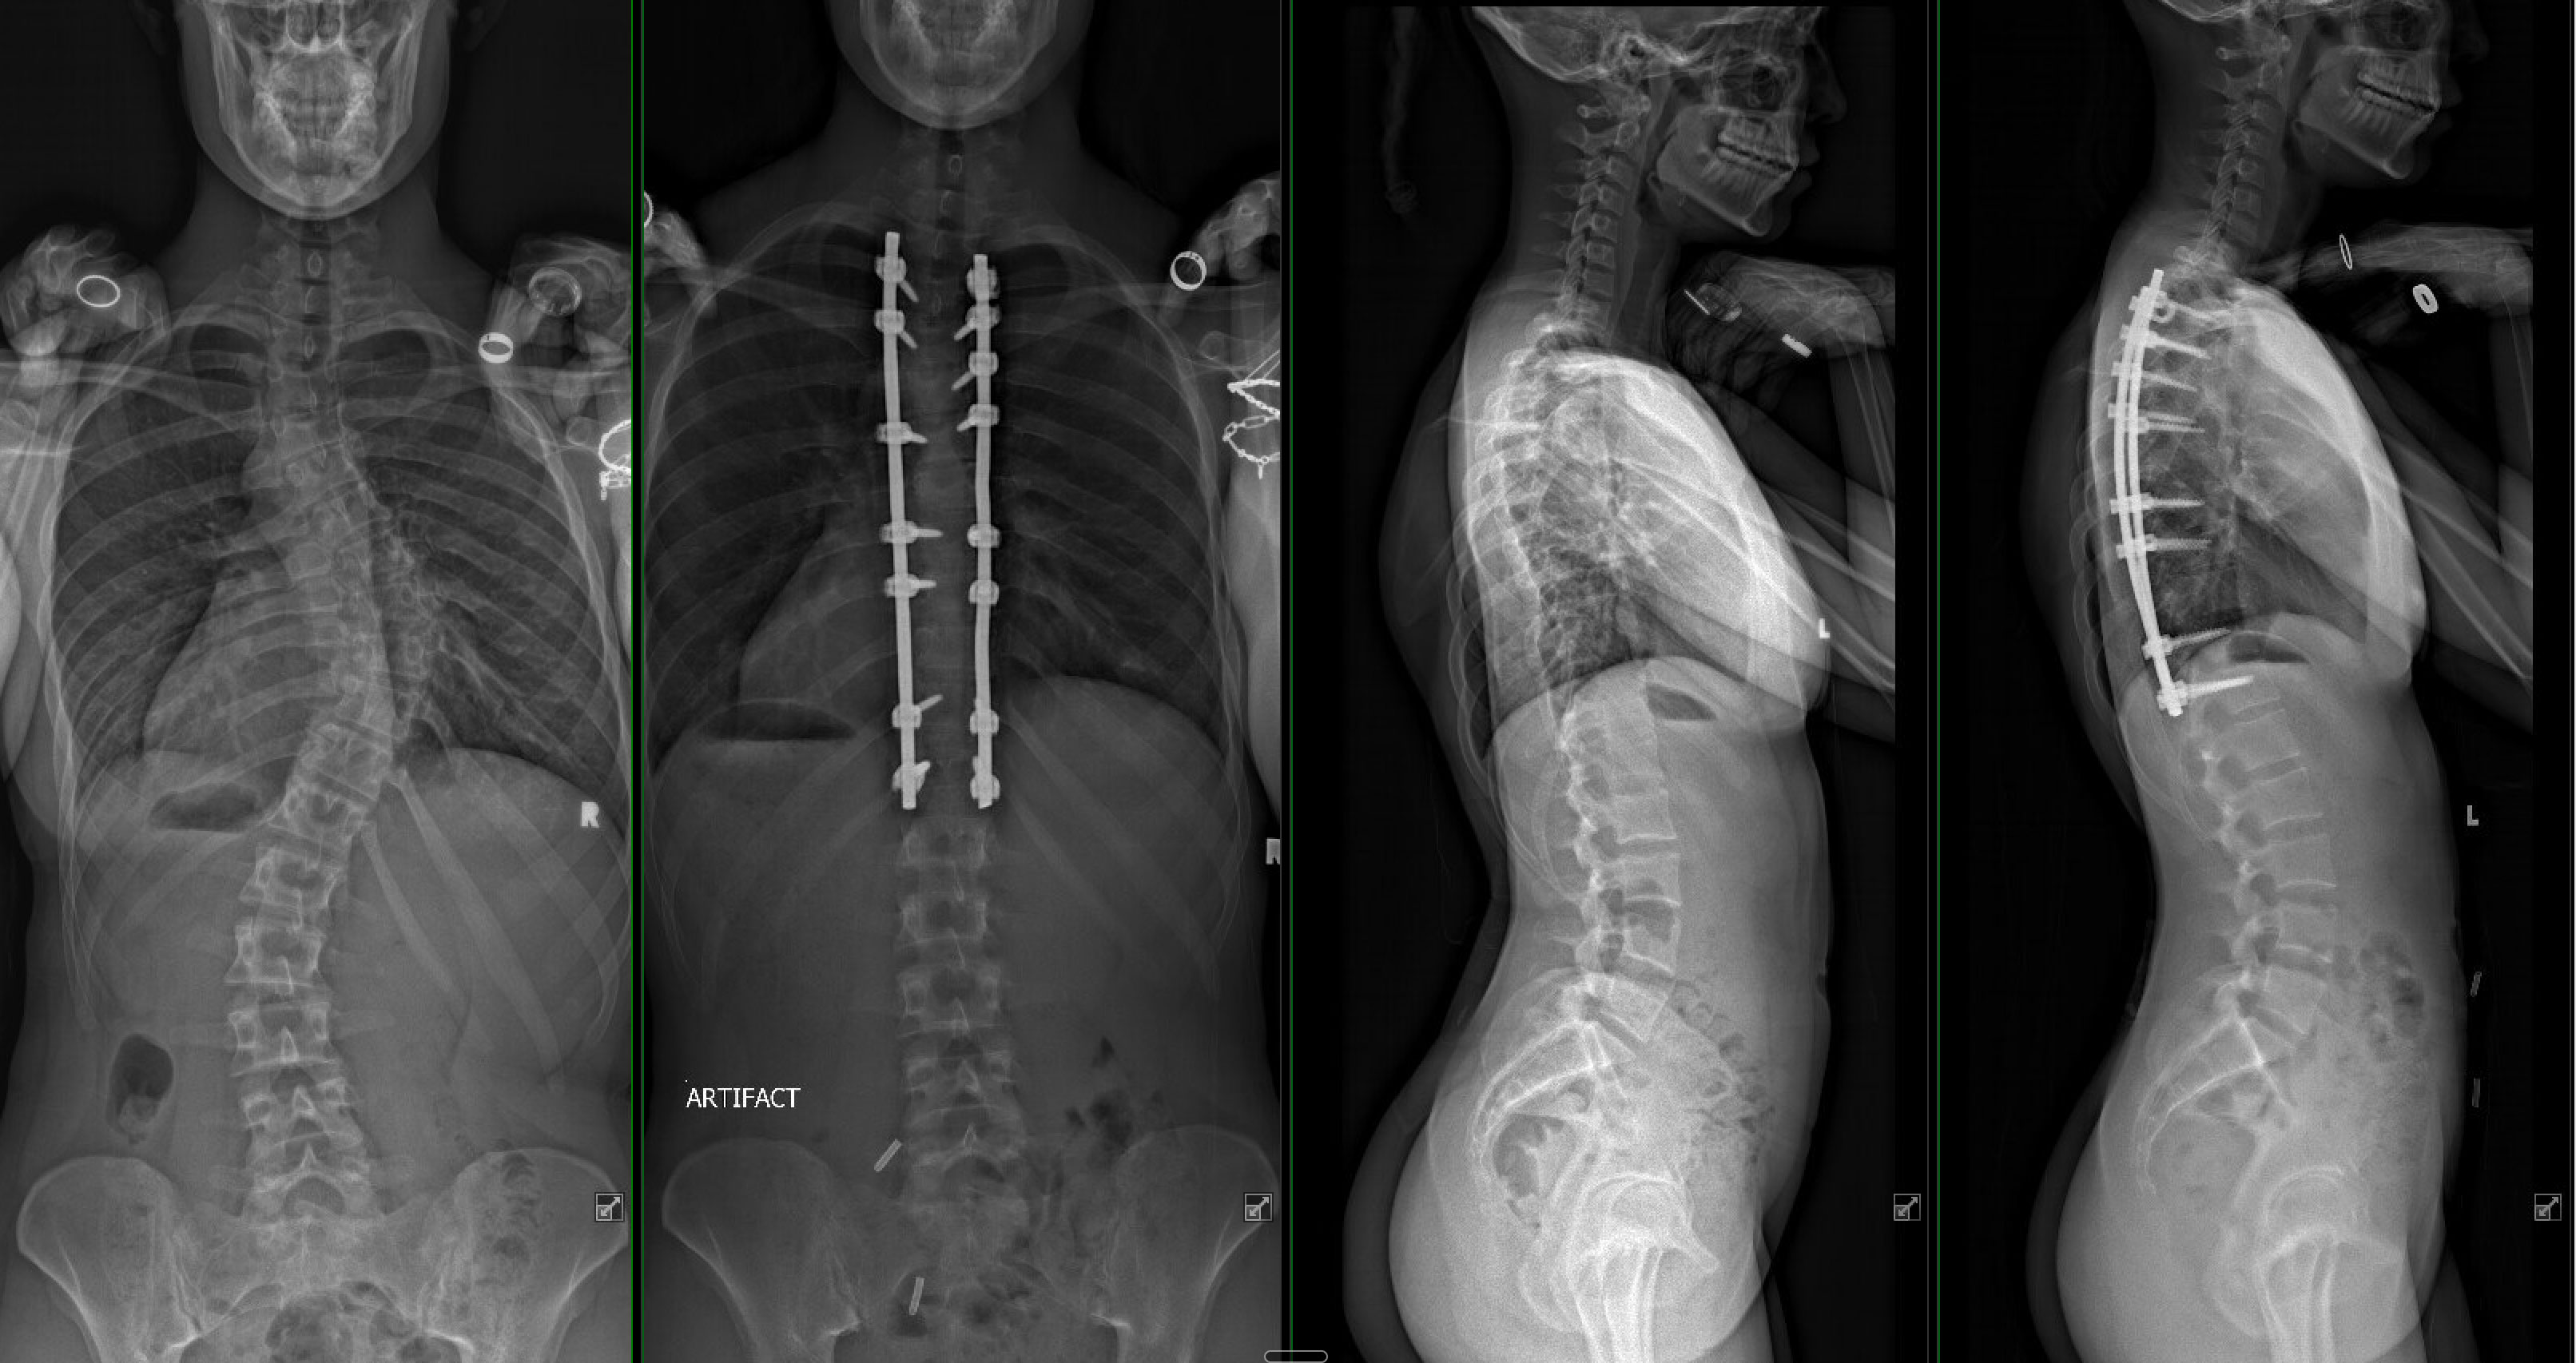

“When Milan came to us, she had three curves in her back, the largest of which was severe, at 53 degrees,” Skaggs said. “Left untreated, it would continue to get one degree worse every year for the rest of her life—eventually leaving her with a huge bump on her back, unable to take a full breath and in a lot of pain.”

When the day finally came for Skaggs to correct Brahney’s scoliosis, he made a single incision—just over ten inches long—down the midline of her back. Through this approach, he placed titanium screws roughly a quarter-inch wide and 1.5 inches long into the vertebrae.

Skaggs and his assistant then gradually and safely straightened Brahney’s spine, and the team secured it with cobalt-chrome rods contoured to match the spine’s natural shape.

The surgery was a success, and eventually, Brahney’s vertebrae will fuse together, supported by the screws and rods.

“They immediately did an X-ray of my back lying down,” she said. “I was really out of it, but I remember looking at it and thinking, ‘Oh my gosh, that’s my spine. It’s straight!’”